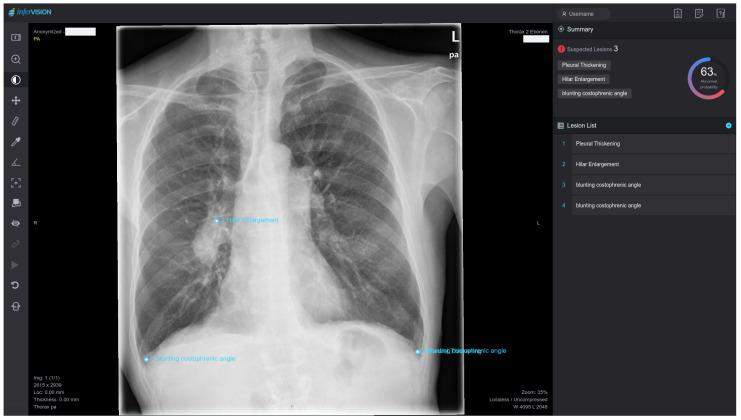

This retrospective study evaluated a commercial deep learning (DL) software for chest radiographs and explored its performance in different scenarios. A total of 477 patients (284 male, 193 female, mean age 61.4 (44.7-78.1) years) were included. For the reference standard, two radiologists performed independent readings on seven diseases, thus reporting 226 findings in 167 patients. An autonomous DL reading was performed separately and evaluated against the gold standard regarding accuracy, sensitivity and specificity using ROC analysis. The overall average AUC was 0.84 (95%-CI 0.76-0.92) with an optimized DL sensitivity of 85% and specificity of 75.4%. The best results were seen in pleural effusion with an AUC of 0.92 (0.885-0.955) and sensitivity and specificity of each 86.4%. The data also showed a significant influence of sex, age, and comorbidity on the level of agreement between gold standard and DL reading. About 40% of cases could be ruled out correctly when screening for only one specific disease with a sensitivity above 95% in the exploratory analysis. For the combined reading of all abnormalities at once, only marginal workload reduction could be achieved due to insufficient specificity. DL applications like this one bear the prospect of autonomous comprehensive reporting on chest radiographs but for now require human supervision. Radiologists need to consider possible bias in certain patient groups, e.g., elderly and women. By adjusting their threshold values, commercial DL applications could already be deployed for a variety of tasks, e.g., ruling out certain conditions in screening scenarios and offering high potential for workload reduction.

这项回顾性研究评估了一款用于胸部X光片的商用深度学习(DL)软件,并探讨了其在不同场景下的性能。共纳入477例患者(男性284例,女性193例,平均年龄61.4(44.7 - 78.1)岁)。作为参考标准,两名放射科医生对七种疾病进行独立解读,共报告了167例患者的226项检查结果。单独进行自动DL解读,并使用ROC分析对照金标准评估其准确性、敏感性和特异性。总体平均AUC为0.84(95%可信区间0.76 - 0.92),优化后的DL敏感性为85%,特异性为75.4%。在胸腔积液方面取得了最佳结果,AUC为0.92(0.885 - 0.955),敏感性和特异性均为86.4%。数据还显示,性别、年龄和合并症对金标准与DL解读之间的一致性水平有显著影响。在探索性分析中,当仅筛查一种特定疾病且敏感性高于95%时,约40%的病例可以正确排除。对于一次性综合解读所有异常情况,由于特异性不足,只能实现边际工作量的减少。像这样的DL应用有望实现胸部X光片的自动综合报告,但目前仍需要人工监督。放射科医生需要考虑某些患者群体(如老年人和女性)可能存在的偏差。通过调整阈值,商用DL应用已经可以用于各种任务,例如在筛查场景中排除某些情况,并具有很大的工作量减少潜力。